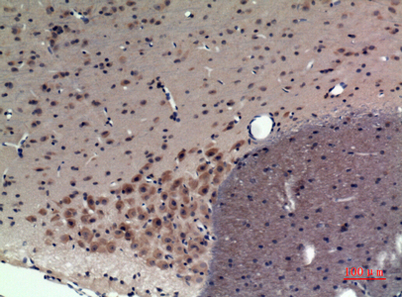

| Dilutions: | Western Blot: 1/500 - 1/2000. Immunohistochemistry: 1/100 - 1/300. Immunofluorescence: 1/200 - 1/1000. ELISA: 1/5000. Not yet tested in other applications. |